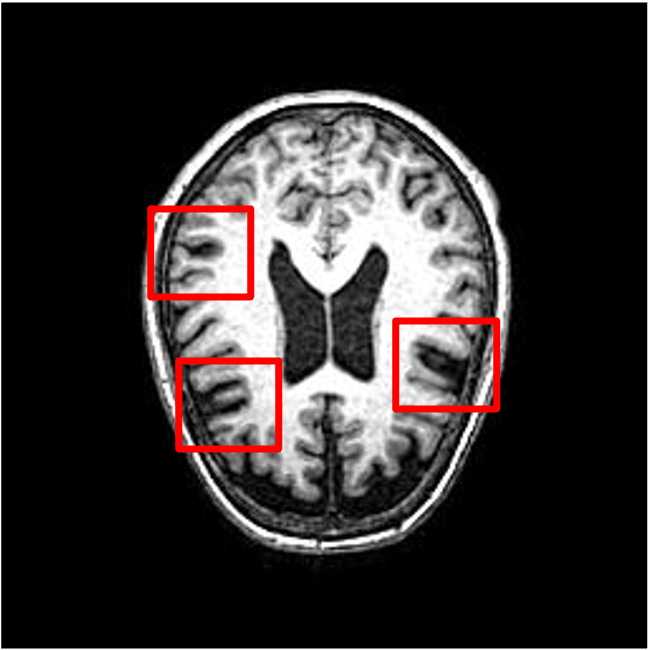

We present the results of conditional medical image generation with and without our proposed method LD, in Tab. 1, and Fig. 5. In Fig. 4, we show examples of brain MR images generated by the different methods combined with LD for two different classes of cognitively normal (CN) and Alzheimer’s disease (AD). The results were obtained by fine-tuning the corresponding method on the medical data with LD. As shown in Fig. 4, the samples generated through Custom Diffusion tuning are realistically looking while understanding the difference between CN and AD brain properly, which other methods failed at. Textual inversion seems to understand the concept but fails to understand the brain structure properly. Quantitative results on the performance of all our methods are presented in Tab. 1. Qualitative results on the CheXpert [19] dataset, along with a user study and ablation of different parameters, optimization algorithm, and more, are included in the supplementary material.

Qualitatively, Fig. 5 shows a significant improvement of the visual realism across all methods when using a drift of . The background is consistently black as in real brain MR images; the shape of the brain becomes more realistic, and the white and gray matter structure improves. For an analytical evaluation, we calculated the FID between our test data and 200 synthetically generated images from each method (100 CN, 100 AD). The results in Tab. 1 demonstrate that LD improves the ability of the model to generate realistic MRI slices for both healthy brains and brains with Alzheimer’s disease. For this reason, all following experiments were done with LD.